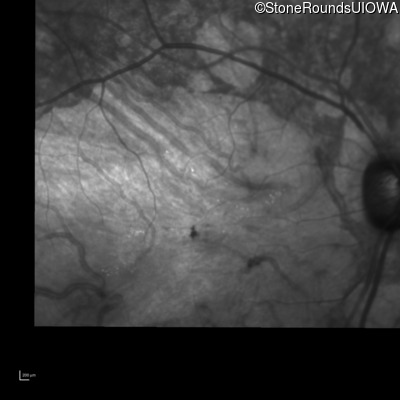

Infrared Fundus Photograph - Left - 10/200 sc

Exemplar